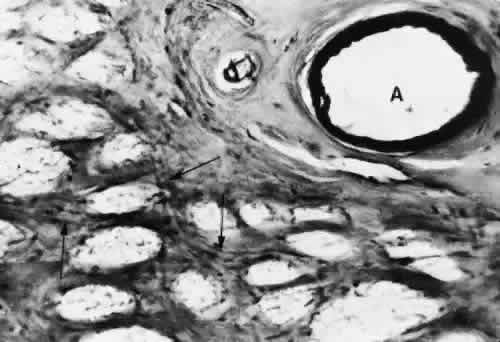

A capillary-free zone is present around each of the larger retinal arteries and veins (Fig. 6). It is more prominent around the arteries, measuring up to 100 μm. The capillary-free zone is a product of the embryologic vascular remodeling process. Direct diffusion of oxygen through the walls of the large retinal vessels probably initiates this process of vascular remodeling. Embryologically, numerous capillary-sized channels retract from the developing artery, leaving only a relatively few right-angled side-arm channels to serve as precapillary arterioles. In keeping these side channels to a minimum, the maintenance of an adequate pressure head for the remainder of the retina is ensured. In contrast, the radial peripapillary capillaries (RPCs) may develop in a different fashion, later than the other capillary beds, after vascular remodeling has already occurred.19

Fig. 6. Human retinal digest preparation. A broad capillary-free zone is present around the artery (A), and a much narrower one is seen about the vein (V) (PAS hematoxylin, × 12). (Wise GN, Dollery CT, Henkind P: Retinal Circulation. New York, Harper & Row, 1971)